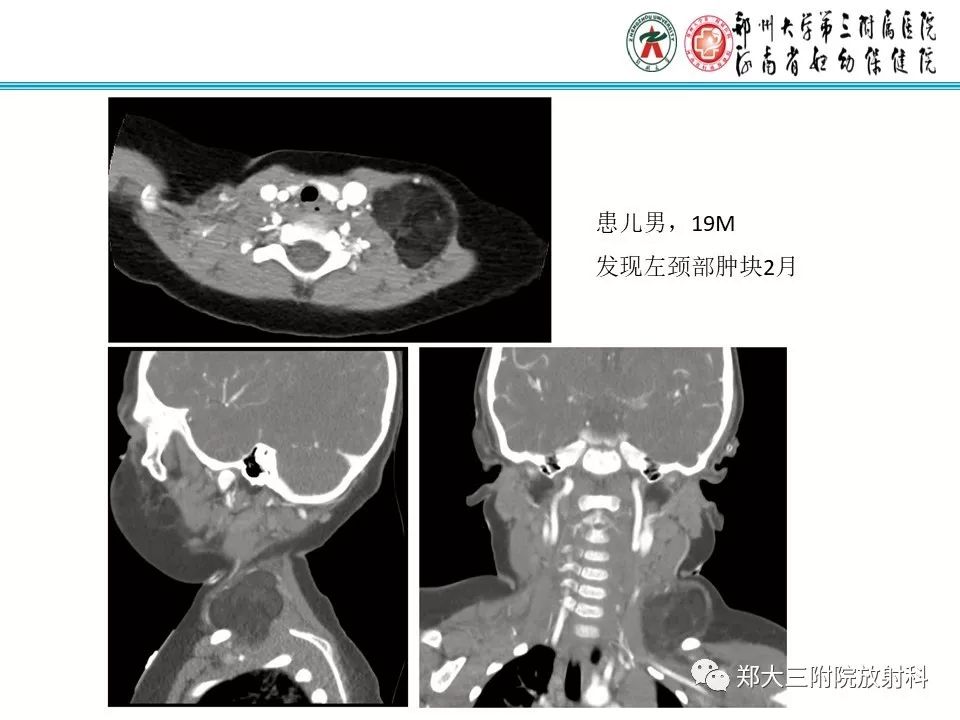

儿童颈部脂肪母细胞瘤1例CT影像诊断

【病例】儿童颈部脂肪母细胞瘤影像诊断